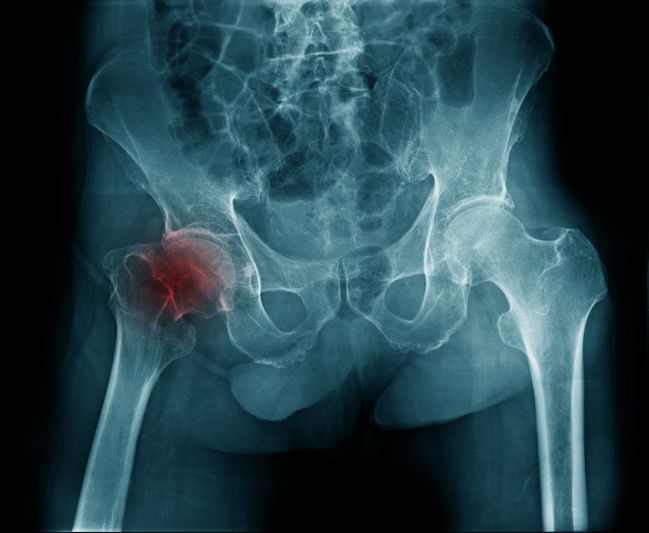

Вколоченный перелом шейки бедра без смещения

Перелом шейки бедра — это довольно тяжелая травма. После нее всегда возникают неприятные осложнения. Для людей преклонного возраста такая травма особенно опасна. Существует мнение, что если произошло повреждение, то это станет сразу очевидным. Суждение не всегда верно, поскольку перелом шейки бедра может быть вколоченным. В этом случае потерпевший сохраняет способность к передвижению в течение следующих нескольких дней. Сигналом того, что произошло повреждение, будет боль в области бедра. Устранить травму и облегчить состояние пациента может только профильный врач.

Вколоченный перелом шейки бедра у пожилых людей

Молодые люди сталкиваются с этим видом повреждений крайне редко. У них такой перелом возникает чаще всего в результате серьезных производственных, спортивных травм или после перенесенных автомобильных происшествий. По статистике, 90 % пациентов с этим повреждением — люди преклонного возраста. Обусловлено это тем, что лица старше 60 лет часто страдают от недостатка кальция в организме. В результате этого развивается остеопороз. Заболевание приводит к хрупкости костей. Малейшее воздействие на них может спровоцировать перелом. Для многих пожилых людей такой вид травмы считается очень опасным, поскольку если его тактика лечения подобрана неверно или помощь оказана не своевременно, то последствия повреждения могут привести к инвалидности, а в некоторых случаях даже к смерти.

При вколоченном переломе шейки бедра происходит смятие костей, и они вклиниваются друг в друга. Эта особенность и дала название травме. При таком переломе человек может передвигаться некоторое время, однако испытывает при этом сильную боль. К прочим симптомам повреждения относятся:

• характерный звук в процессе деформации;

• боль в области травмы, иногда она может отдавать в пах;

• трудности при передвижении;

• поврежденная конечность значительно короче, чем здоровая;

• невозможность приподнять больную ногу.

Пациент со вколоченным переломом, когда переворачивается на кровати, слышит характерный хруст в тазобедренном сочленении. Если ему постучать легонько по пятке больной конечности, то боль усиливается и иррадиирует в пах. При осмотре потерпевшего в положении лежа ступня поврежденной ноги находится в наружной ротации. Самостоятельно вправить стопу не представляется возможным.

К сожалению, такие симптомы могут долгое время игнорироваться человеком. Он продолжает перемещаться, и не обращается за помощью к врачу. В результате такого поведения, вколоченный перелом нередко трансформируется в обычный. Он уже требует гораздо более серьезного лечения и длительного реабилитационного периода.

Вколоченный перелом шейки бедра без смещения — считается одной из более благоприятных форм. Проявляется болью в тазобедренной области и ограничением движений. Без терапии возможны осложнения и переход в открытый перелом. Также усиливается риск нарушения кровоснабжения головки бедренной кости. Это состояние требует ограничения нагрузки и длительной иммобилизации. Без терапии возможны остеонекроз и хроническая боль.